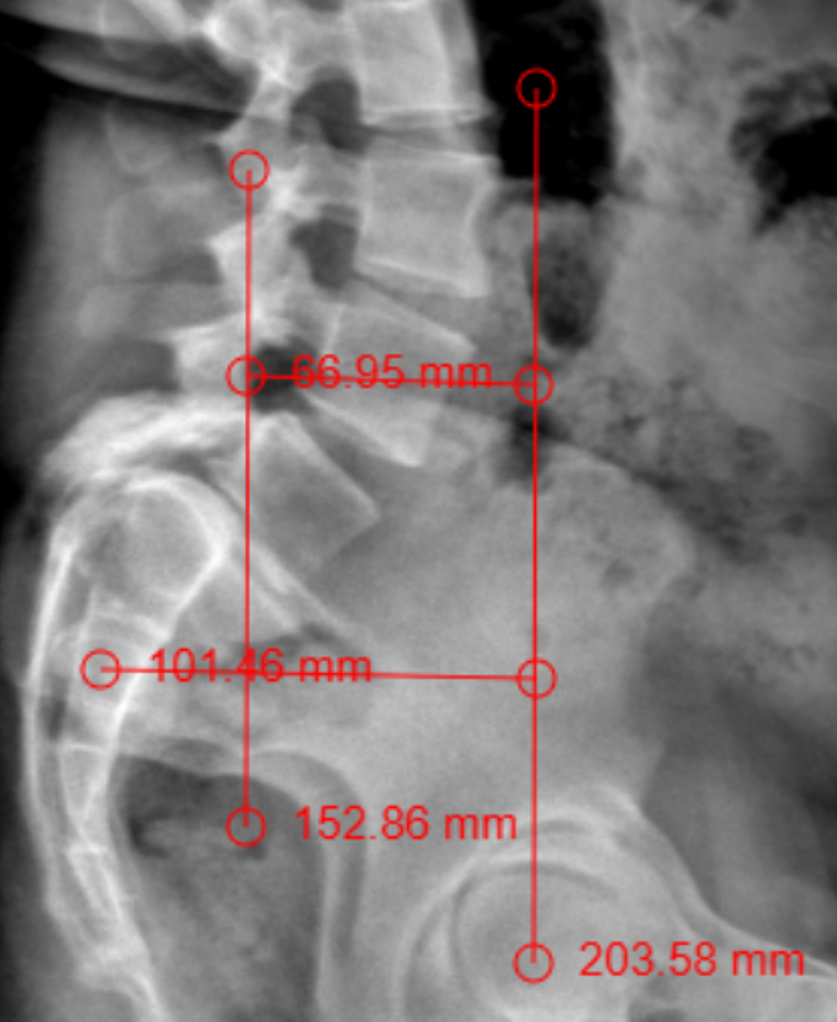

The patient had lumbar spine tenderness localized over the L4 and L5 vertebral levels. Lumbar spine range of motion (ROM) is painful on flexion and extension. Neurological examination showed positive Lasegue’s test at 40° on the right and 30° on left. Motor examination (5/5) in L1, L2, and L3 myotome bilaterally, with reduced power (4/5) in the L4, L5, and S1 myotome on both sides. Sensory examination showed normal sensation in the L1, L2, and L3 dermatomes, reduced sensation on the left at L4, and reduced sensation bilaterally at L5 and S1 S2 S3 S4 S5. Reflex examination showed diminished knee and ankle reflexes and plantar was mute on both side. MRI of lumbar spine with whole spine screening showed anterior listhesis of L5 over S1,central disc bulge,hypertrophy of the facet joints and ligamentum flavum caused severe central canal stenosis, lateral recess narrowing, compression of cauda equina roots, and severe bilateral foraminal stenosis with impingement of the exiting L4 nerve roots bilaterally (Figure1). Post-void residual urine volume is 232 cc on ultrasonography. Diagnosis was high dysplastic spondylolisthesis of L5 over S1, Meyerding Grade III, SDSG – Type 5 balance spine retroverted pelvics based on pelvic incidence 70o pelvic tilt 38osacral slope 32o (Figure 2). The high dysplastic according to the severity index.The patient was counseled on the need for immediate surgical decompression and lumbosacral stabilization to stop neurological deterioration. The recovery of bladder and bowel function was explained to be guarded due to the chronicity of symptoms. After getting informed and written consent the patient underwent posterior decompression and spondylolisthesis reduction with stabilization from L4 to S1, along with bilateral posterolateral fusion at L4-L5-S1 and posterior interbody fusion at L5-S1 under general anesthesia.We fixed L4 also, as the current case is an unstable zone.This zone was identified using a standing lateral radiograph of the lumbar spine that also captures the hips.On radiograph, square area is demarcated by drawing a horizontal line through the center of the S2 vertebral body. The boundaries of the line segment are determined by two vertical reference lines: one is the gravity line, which runs vertically through the midpoint of the inferior endplate of L5, and the other represents the ground reaction force, passing vertically through the center of the femoral head (Figure 3).

Figure 2